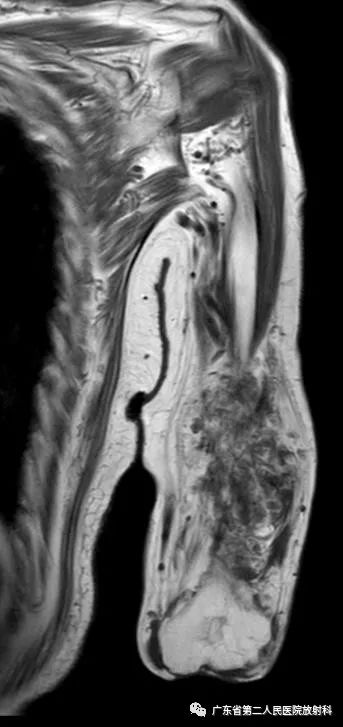

T1WI

左上肢前壁截肢术后观,左上臂中下段见团块状异常信号,病灶信号明显不均,整体以长T1长T2信号影为主,增强扫描呈明显不均匀强化,末端球形膨大,内见散在少许团絮状短T2长T1且无强化信号。冠状位示病灶整体呈梭形改变,边界欠清,部分包绕肱骨下段,以长T1长T2信号为主,散在少许短T2信号,增强扫描明显不均匀强化,内见散在少许团絮状短T2长T1且无强化信号。肱骨下端边缘欠光整,骨髓未见明确异常信号。